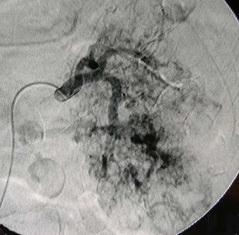

肾癌出血栓塞(明胶海绵块+弹簧栓子)

明胶海绵块主要用于作为控制创伤出血,胃肠道出血,肝、肾和肺出血及阻断不同器官肿瘤血供的栓塞剂。通常在栓塞4-6周后,明胶海绵潜在被吸收的可能[2]。 明胶海绵块 :是指手术台上手工将成品的明胶海绵片剪成的明胶海绵碎片